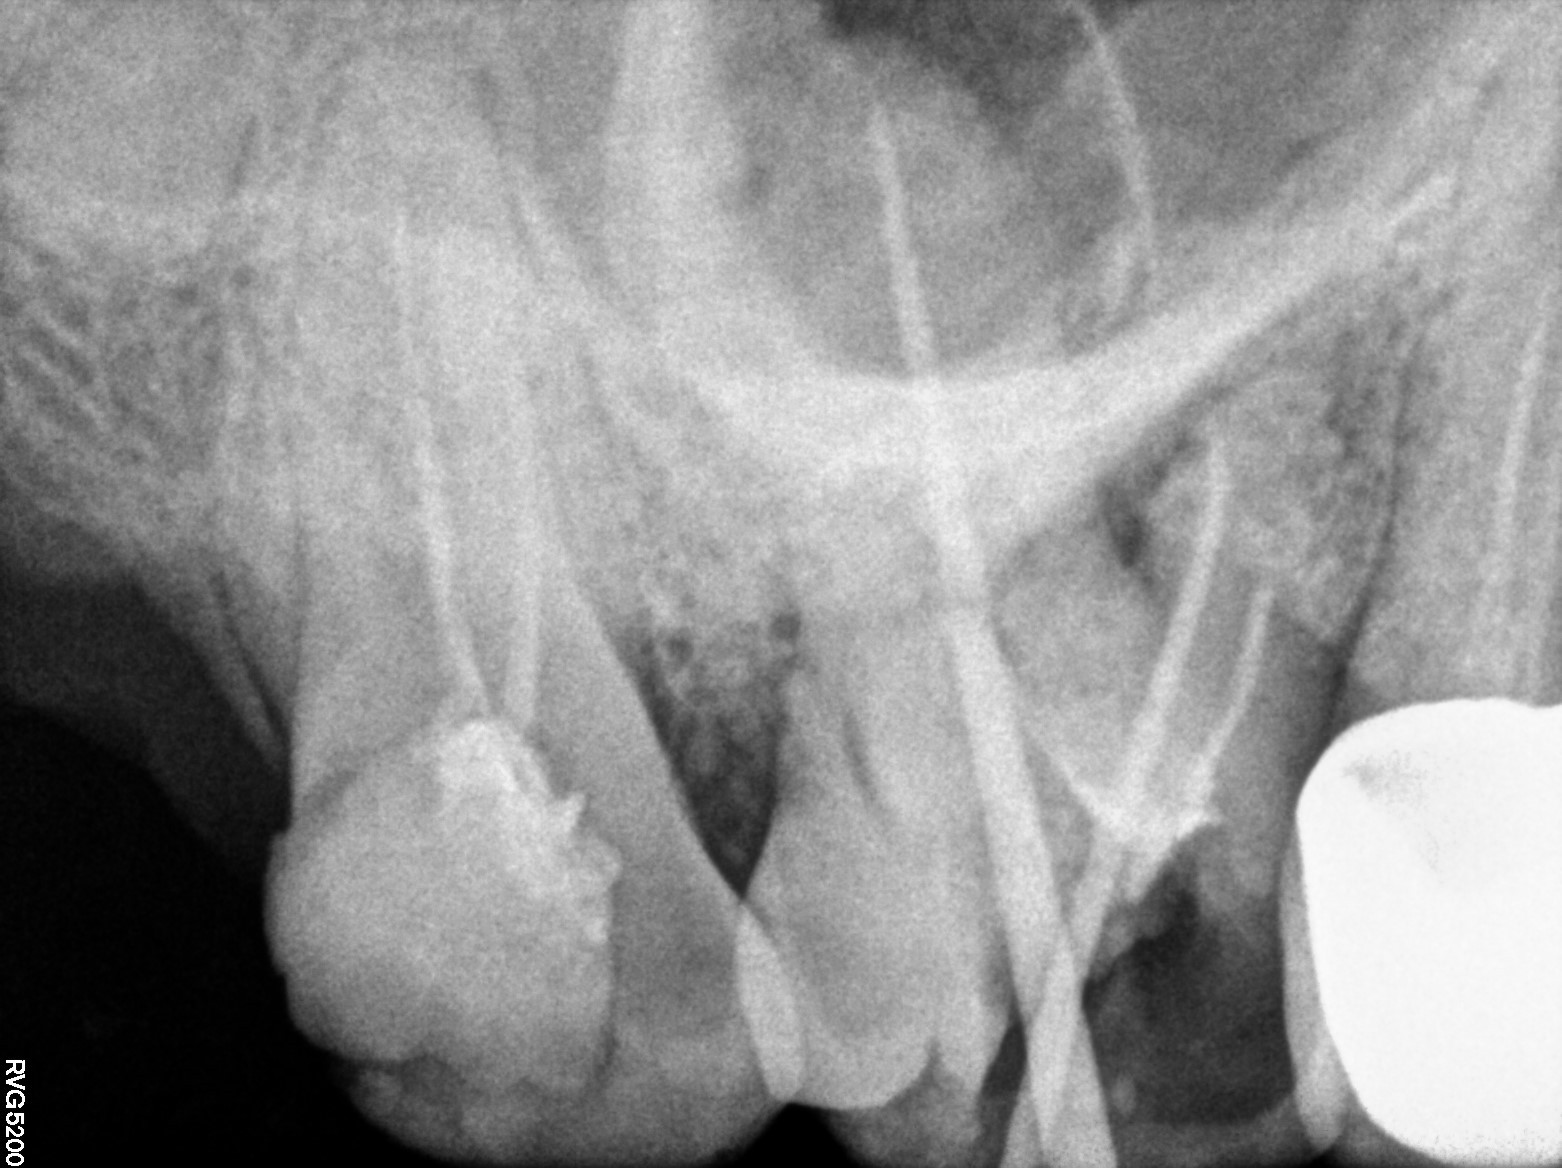

Dental Radiographs FHIR: DocumentReference · LOINC 24641-7

xray_1773040794_0.jpg

24641-7